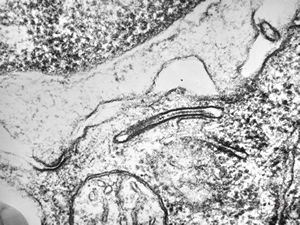

M, 43y. | myeloid leukemia … Auer bodies